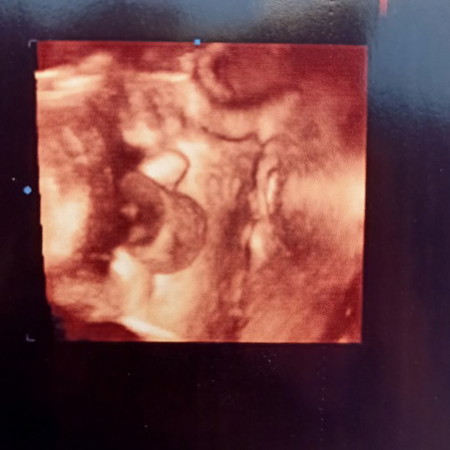

กำหนดคลอด 26 ก.พ 63 ผมเป็นเด็กผู้ชายครับ แม่ๆท่านไหนคลอดเดือนกุมภาบ้างค่ะ เพศไหนและกี่สัปดาห์กันแล้วเอ่ย